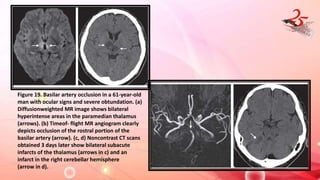

Figure 19. Basilar artery occlusion in a 61-year-old

man with ocular signs and severe obtundation. (a)

Diffusionweighted MR image shows bilateral

hyperintense areas in the paramedian thalamus

(arrows). (b) Timeof- flight MR angiogram clearly

depicts occlusion of the rostral portion of the

basilar artery (arrow). (c, d) Noncontrast CT scans

obtained 3 days later show bilateral subacute

infarcts of the thalamus (arrows in c) and an

infarct in the right cerebellar hemisphere

(arrow in d).

Figure 19. Basilarartery occlusion in a 61-year-old man with ocular signs and severe obtundation. (a) Diffusionweighted MR image shows bilateral hyperintense areas in the paramedian thalamus (arrows). (b) Timeof- flight MR angiogram clearly depicts occlusion of the rostral portion of the basilar artery (arrow). (c, d) Noncontrast CT scans obtained 3 days later show bilateral subacute infarcts of the thalamus (arrows in c) and an infarct in the right cerebellar hemisphere (arrow in d).